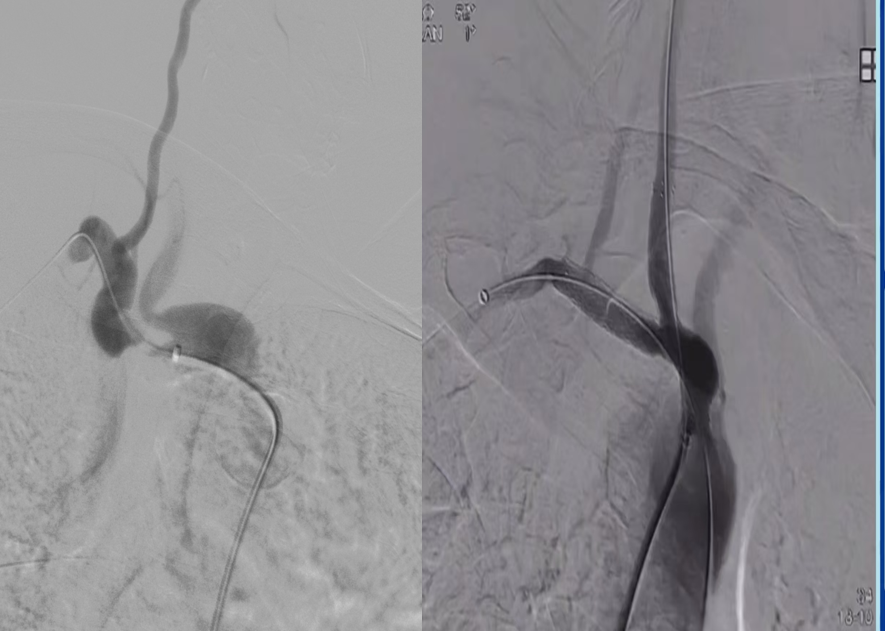

病例三

常规病变的精准支架释放:

即使是常规狭窄病变,采用CTA预定的角度(如 RAO 50° CRA 0°)也能实现支架的精准释放,确保完全覆盖病变且不影响重要分支。

图:CTA确定投射角度

图:支架精准释放

图:术中验证